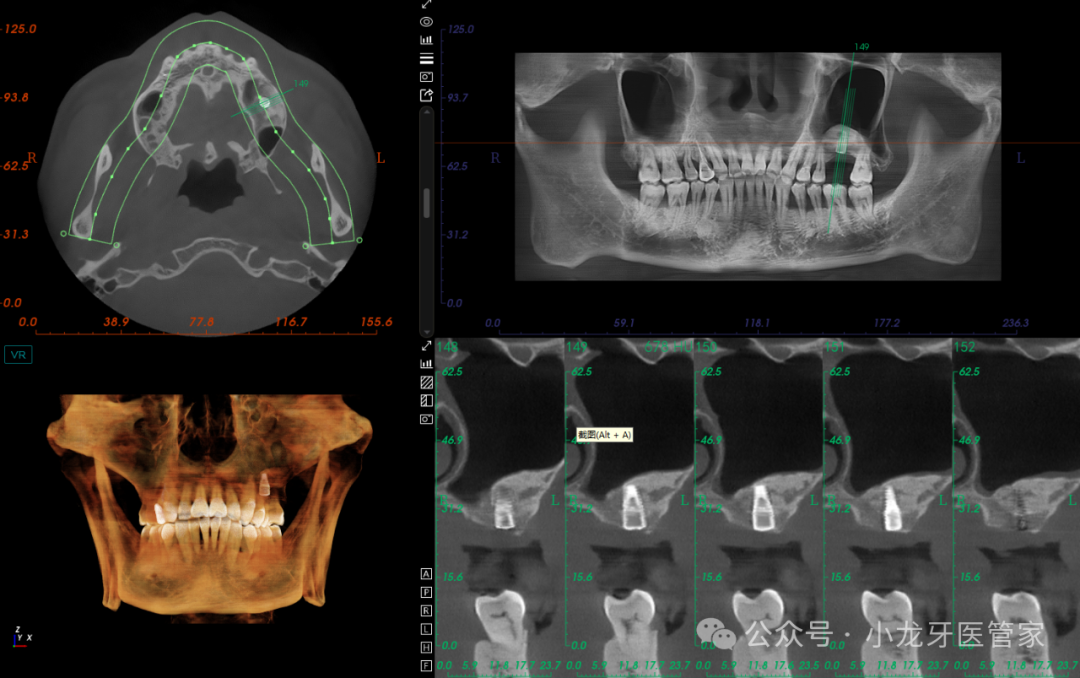

辅助检查:CBCT示左上颌窦较为宽大,窦底剩余骨高度约2mm,窦黏膜厚度约1.5mm,窦腔未见液平面,上颌窦外侧壁骨板完整。

术后当天影像学图片

(CT上看,因整体窦腔空间较为宽大,0.75g骨粉的植入面积稍欠)